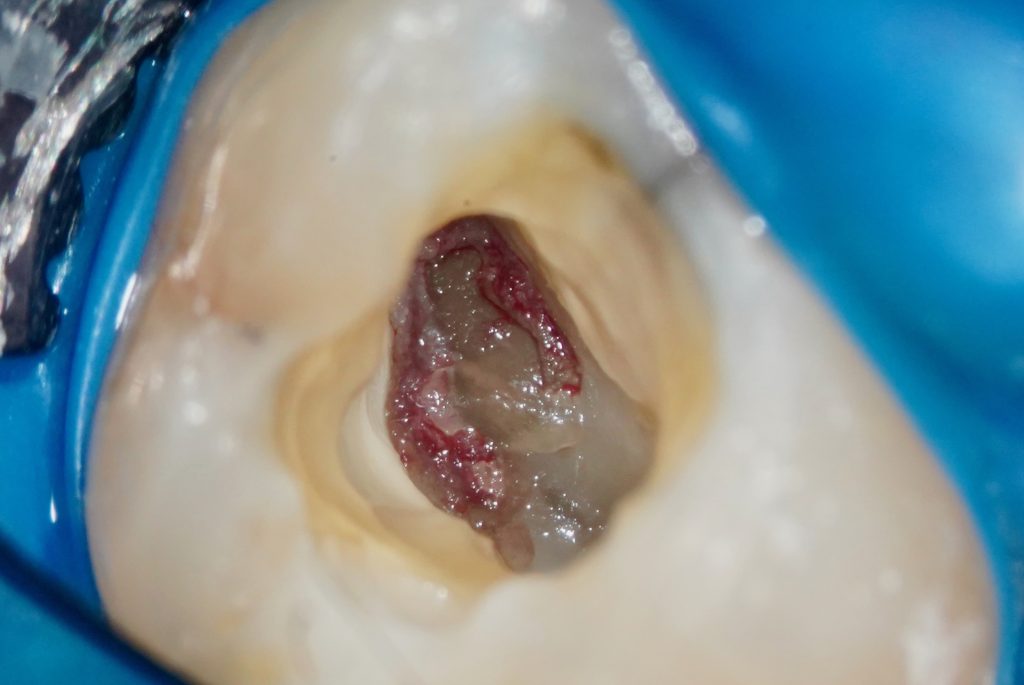

Critères de confirmation en peropératoire : saignement abondant à l’ouverture de la chambre, hémostase obtenue après descente mécanique de 1 à 3 mm dans les canaux.

Le seul élément fiable en cours d’acte est l’hémostase. Un tissu pulpaire sain saigne franchement à l’amputation puis s’arrête spontanément ou très rapidement après rinçage. Un tissu inflammatoire saigne en continu, de manière diffuse, sans s’arrêter.

La qualité de l’hémostase — instantanée, sans compression — est le vrai critère de sélection per-opératoire, bien plus que les symptômes pré-opératoires. Pour approfondir cette notion, consultez notre article sur l’hémostase mécanique en pulpotomie.